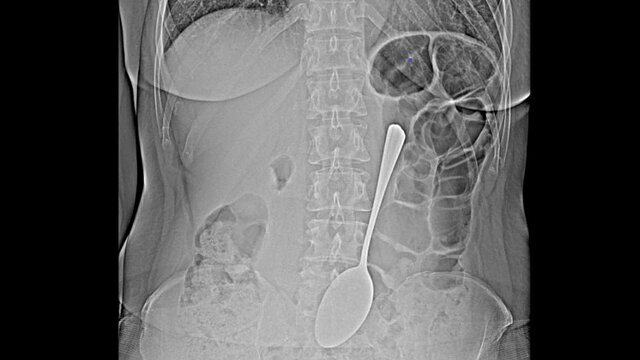

В Улан-Удэ медики спасли пациентку, которая проглотила столовую ложку